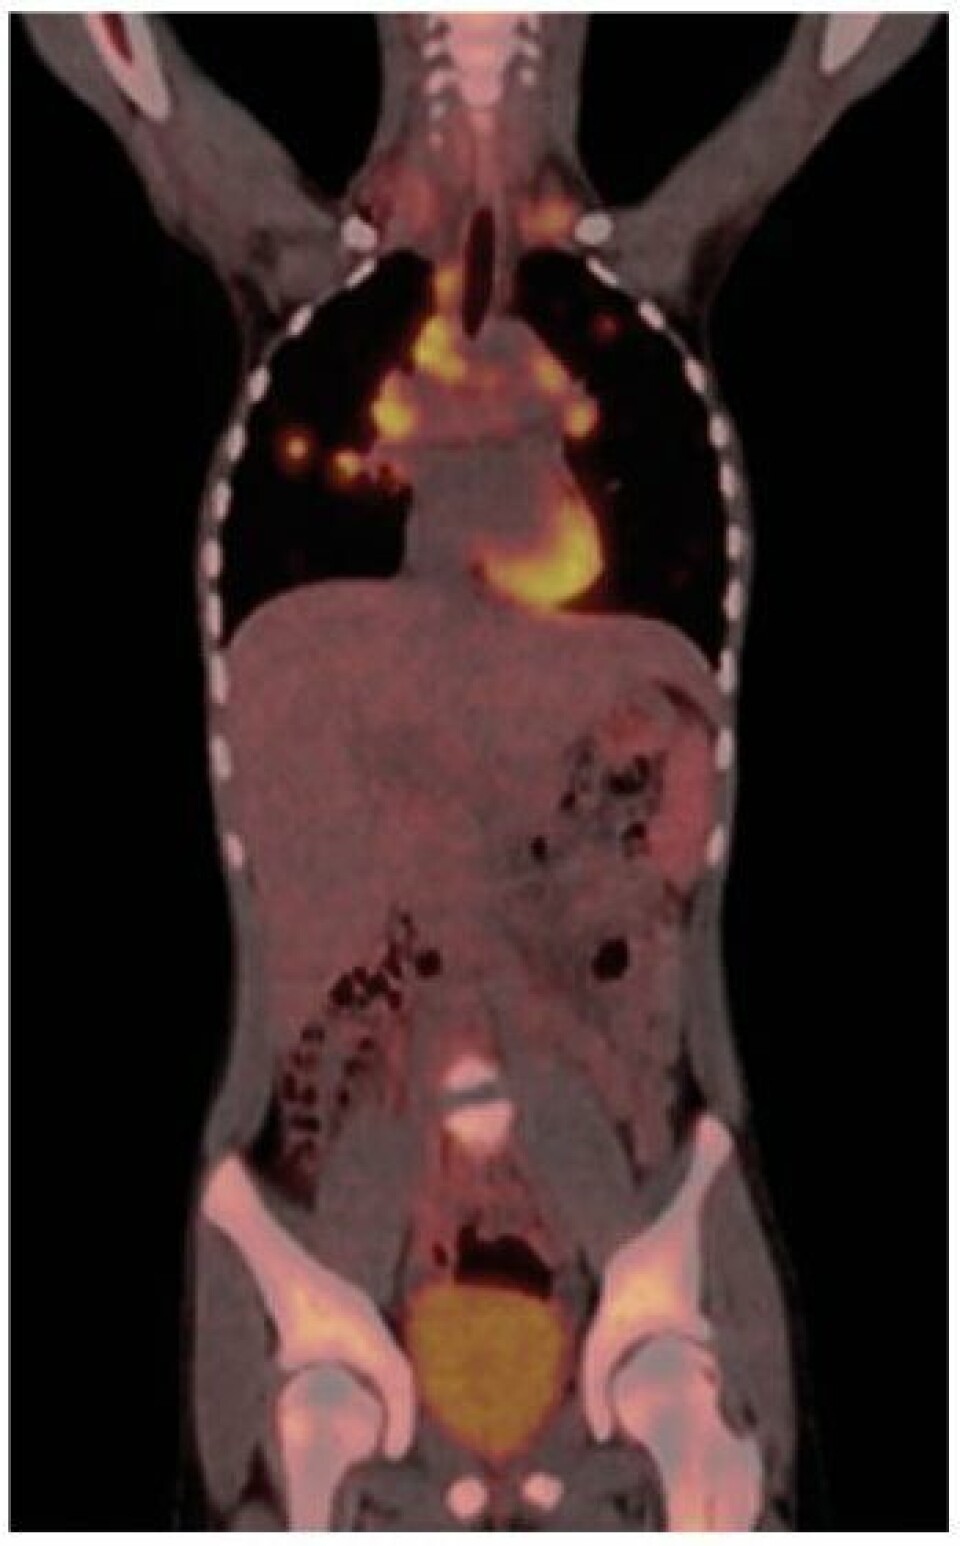

I 1978 ble den første SPECT (single photon emission computer tomography)-skanneren tatt i bruk ved Rikshospitalet. Det første koinsidenskamera, som var forløperen til PET (positron emission tomography)-skanneren, ble installert i 1998 ved Radiumhospitalet. På 2000-tallet kom begrepet hybridkamera inn i den nukleærmedisinske terminologien. Det vil si et kamera som består av en nukleærmedisinsk (NM) del koblet sammen med en computertomografi (CT)-del. Med slike kamera kan man korrigere for attenuasjon og bedre lokalisere NM-funnet, ved at man får en kombinert avbildning av fysiologi og anatomi.

Siden 2005 har PET/CT blitt et etablert tilbud ved flere nukleærmedisinske enheter i Norge. Trondheim har Norges eneste PET/MR. Sykehuset Østfold får høsten 2016 installert den første digitale PET/CT i Norge, Ahus får den i løpet av 2017 og flere følger etter.

I dag er det scintigrafi (SPECT/CT og PET/CT) innenfor feltene onkologi, nevrologi og kardiologi som dominerer faget. Terapeutisk bruk av radionuklider er fremdeles en del av hverdagen ved nukleærmedisinske avdelinger. 131I har vært brukt i behandling av hyperthyreoidisme og thyreoideacancer siden 1950, og er fremdeles like aktuelt i dag. Andre nuklider er også brukt innen terapi, blant annet 177Lu, 153Sm og 90Y. Nylig ble 223Ra tatt i bruk som livsforlengende behandling av cancer prostata med skjelettmetastaser (3).